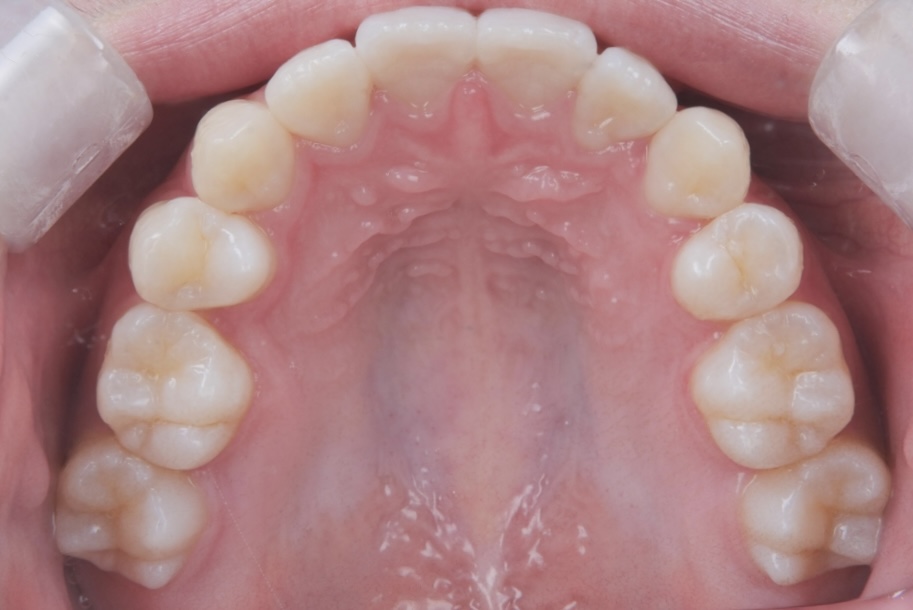

高校生女性 八重歯と噛み合わせが気になる

高校生の女性の患者さまで、初診時は15歳でした。八重歯と噛み合わせの乱れを主訴にご相談に来院されました。歯並びについて意識するようになったきっかけは、学校の歯科健診で矯正治療をすすめられたことだったそうです。

当院では、年齢や成長段階を正確に評価したうえで治療計画を立案し、カリエール装置を併用したマウスピース矯正を行いました。当院ではマウスピース矯正を専門的に数多く手がけてきた経験をもとに、見た目だけでなく噛み合わせの改善まで含めた治療を進めています。

治療期間は1年7ヶ月で、高校生のうちに矯正治療を終えることができました。

八重歯や噛み合わせが整い、口元の印象が大きく改善しています。治療後には、矯正中のモチベーション維持や経過確認がしやすかった点、想定よりも早く治療を終えられたことについて、嬉しい口コミもお寄せいただきました。

AFTER